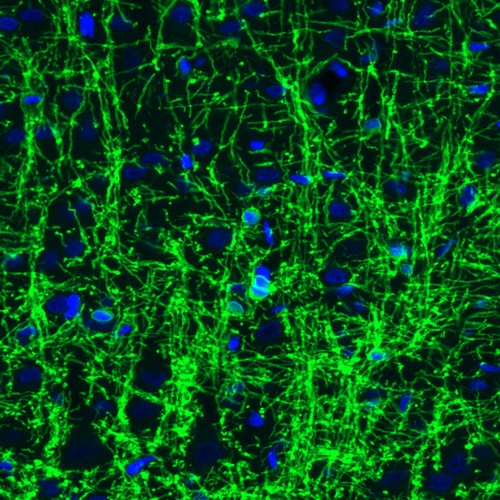

Immunohistochemistry analysis in human cerebral cortex and liver tissues using AMAb91068 antibody. Corresponding CNP RNA-seq data are presented for the same tissues.